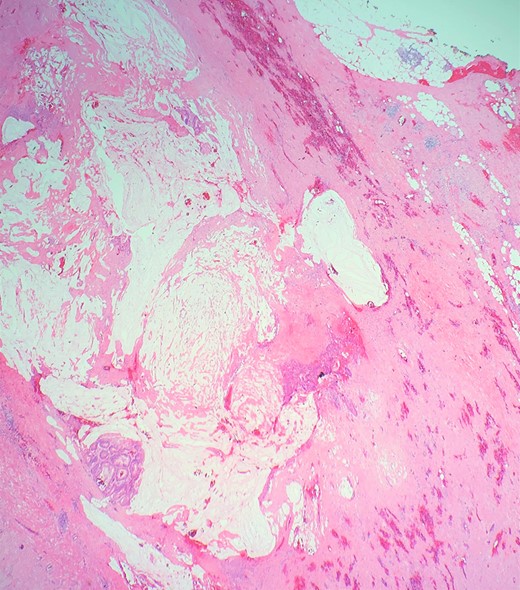

Definitive histological examination showed perforated appendix involved by moderately differentiated mucinous adenocarcinoma (Fig. 5), arising in the background of diffuse tubulovillous adenoma with extensive high-grade dysplasia and showed cellular mucin within the periappendiceal soft tissue (Figs 6 and 7). Proximal cecal mucosal margin and mesenteric margin uninvolved by carcinoma and four periappendicular lymph node was negative for metastatic carcinoma and pathological stage aided for pT4a, pN0. The post-operative course was uneventful. The tumor was staged as T4N0M0 (Modified Astler Coller B3). Patient was referred for oncology and for multidrug adjuvant chemotherapy of 5-fluorouracil, lecovorin and oxalipatin (FOLFOX) was given. Patient was asymptomatic during the 2 weeks, 3 months and 6 months follow up.

Shows transition of normal cecal mucosa to high-grade tubulovillous adenoma at the appendiceal orifice.